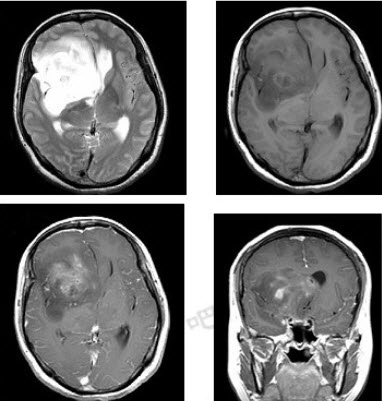

女,32岁,头痛1年,复视4个月,请根据所提供图像,选择最可能的诊断()

A:(右额颞)胶质母细胞瘤

B:(右额颞)多形性黄色星形细胞瘤

C:(右额颞)混合性胶质瘤(星形细胞和少突细胞)

D:(右额颞)毛细胞型星形细胞瘤

E:(右额颞)室管膜下巨细胞星形细胞瘤